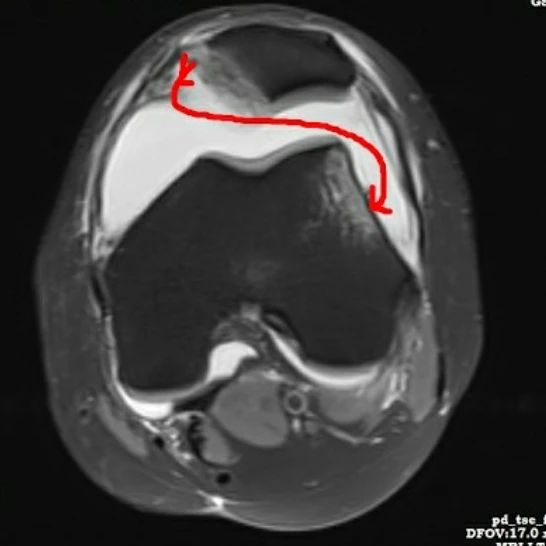

Grade III medial patellofemoral ligament tear at patellar attachment.